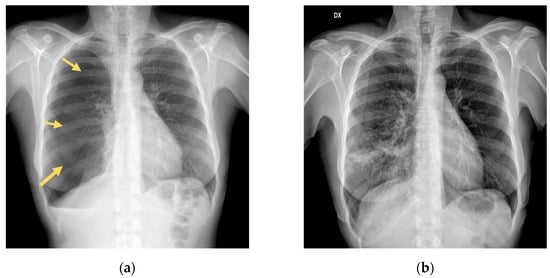

2. Case Presentation